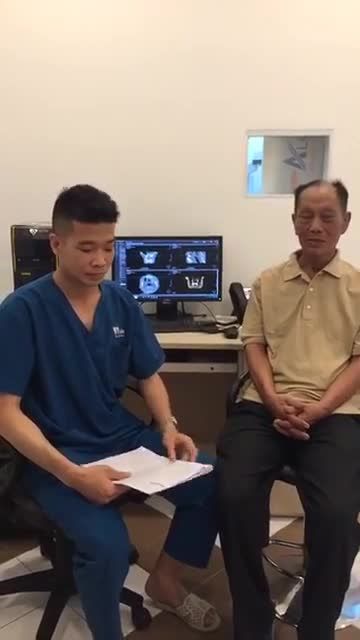

Chú khách hàng đến với Nha khoa Paris trong tình trạng bị sâu răng nặng dẫn đến lung lay và mất nhiều răng. Sau khi thăm khám kỹ lưỡng, bác sĩ Phan Tiến Hoài đã chỉ định cấy ghép 5 trụ implant để khôi phục lại hàm răng, cải thiện chức năng ăn nhai.

Trồng răng Implant là một kỹ thuật khó đòi hỏi tay nghề cao, chuyên môn sâu và dày dạn kinh nghiệm. Vì thế các khách hàng thông thái cần lựa chọn đúng cơ sở uy tín để thực hiện phẫu thuật, tránh xảy ra sai sót.